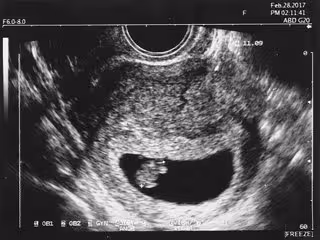

Archivo - El tejido pulmonar fetal muestra una firma microbiana bacteriana ya a las 11 semanas de gestación

Archivo - El tejido pulmonar fetal muestra una firma microbiana bacteriana ya a las 11 semanas de gestación - UNIVERSITY OF ALABAMA AT BIRMINGHAM - Archivo